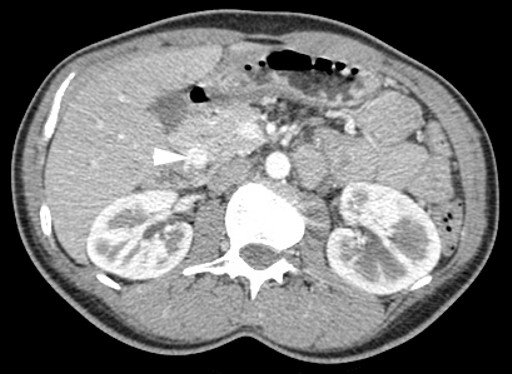

A 37-year-old Caucasian female was referred with a one-year history of recurrent right upper quadrant pain associated with sweating and nausea. She also had symptoms of hot flushes and palpitations, but no diarrhoea or weight loss. There was no significant past medical history or family history. Physical examinations were unremarkable. Initial investigations revealed normal full blood counts, urea and electrolytes, liver function tests and coagulation screen. Her gut hormone profile was normal, as were chromogranin A and B levels. Abdominal ultrasonography showed sludge within the gallbladder as well as a lesion in the head of the pancreas. Abdominal computed tomography (CT) scans showed a 2 cm hypervascular lesion lying between the head of pancreas and the second part of the duodenum (Figure 1). Endoscopic ultrasound scan (EUS) revealed a 1.8x1.5 cm hypervascular lesion in the head of the pancreas. No endoscopic fine-needle aspiration (FNA) cytology was carried out as the lesion appeared very vascular and the risk of bleeding was not warranted given the plan for operative excision. No specific mucosal abnormalities were reported in the duodenum. A pre-operative diagnosis of either a neuroendocrine or a solid pseudopapillary tumor of the pancreas was made based on the imaging findings.

Figure 1. Abdominal computed tomography scan showing 2 cm hypervascular mass lying between the head of the pancreas and the second part of the duodenum easily mistaken for a neuroendocrine tumor or ductal adenocarcinoma. |